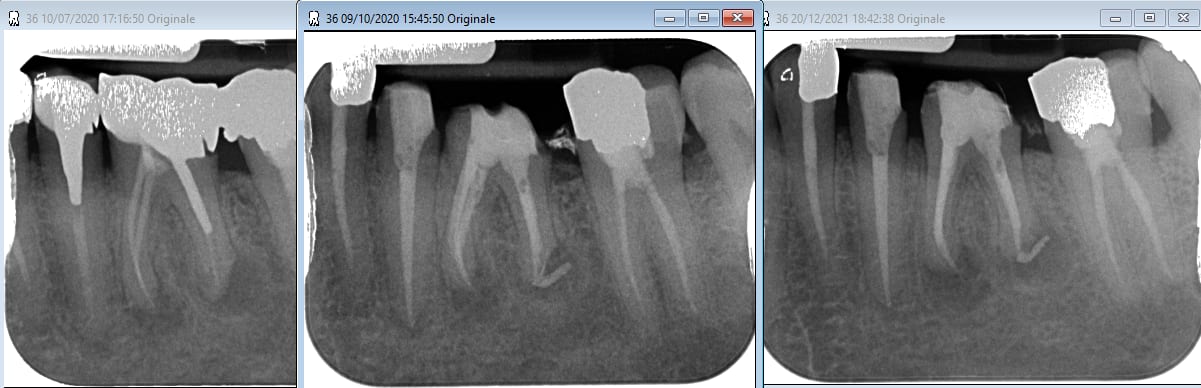

le nombre de fois où le CBCT nous montre des lésion interradiculaires non visibles sur les rétros ...

Ci-joint sur une reprise de traitement, où le cone Beam révélait une fenêtre vestibulaire et un plancher absent, et un mv2 absent.

Retraitement de 17 et 16 en 2 temps.

La 17 retraitée en janvier présentait un canal MV en lame de couteau, comme décrit plus haut. La radio n'était pas si affolante que ça quant à la qualité du précédent traitement, et pourtant j'ai sorti des kilos de merde du canal.

La 16 présentait un MV2 distinct, non traité, mais qui ne semblait pas "visuellement" infecté.

La patiente a fait un covid il y a 10 jours, et me décrit au téléphone une récidive de l'infection de 17.

Elle se sent gonflée dans la zone, peut-être faudra-t-il extraire.

Des fois, même quand le traitement semble propre, ça veut pas.